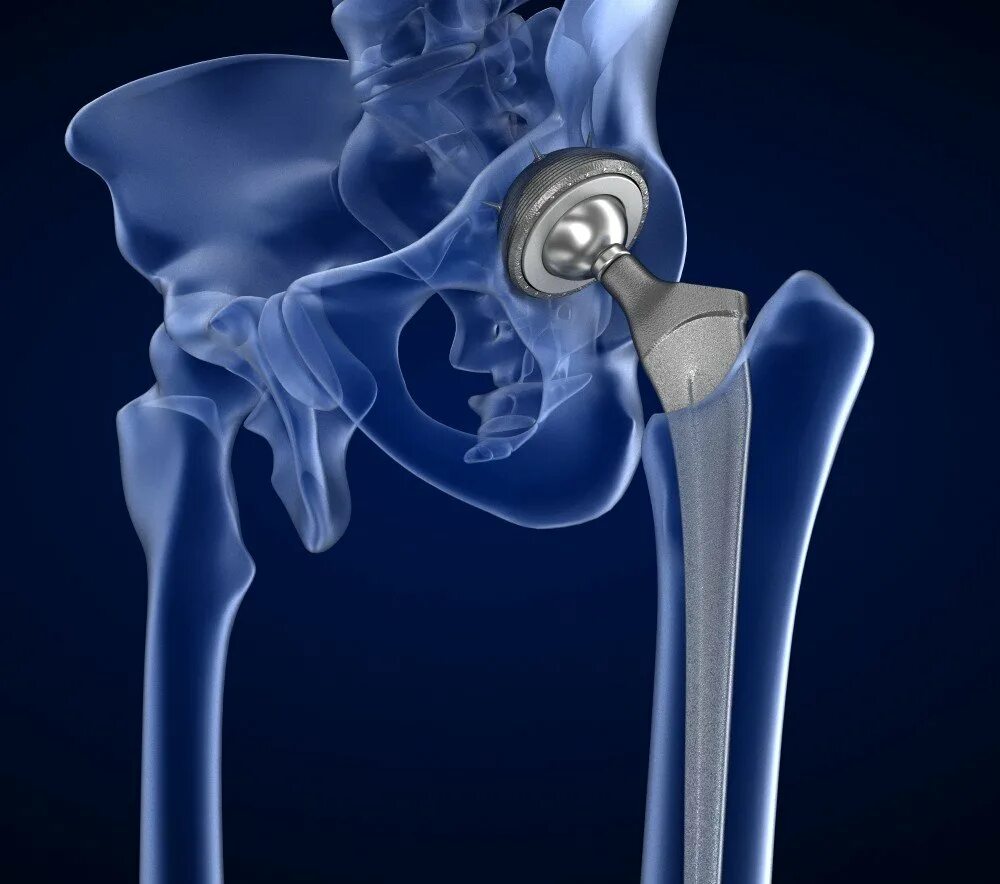

Протезирование тазобедренного сустава видео